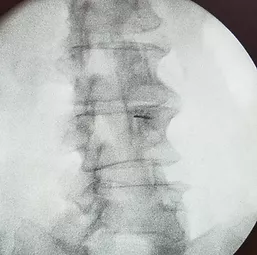

Процедура проходит под постоянным рентгенологическим контролем, поэтому максимально безопасна для пациента.

На рентгене справа показано положение иглы в полости межпозвонкового сустава.